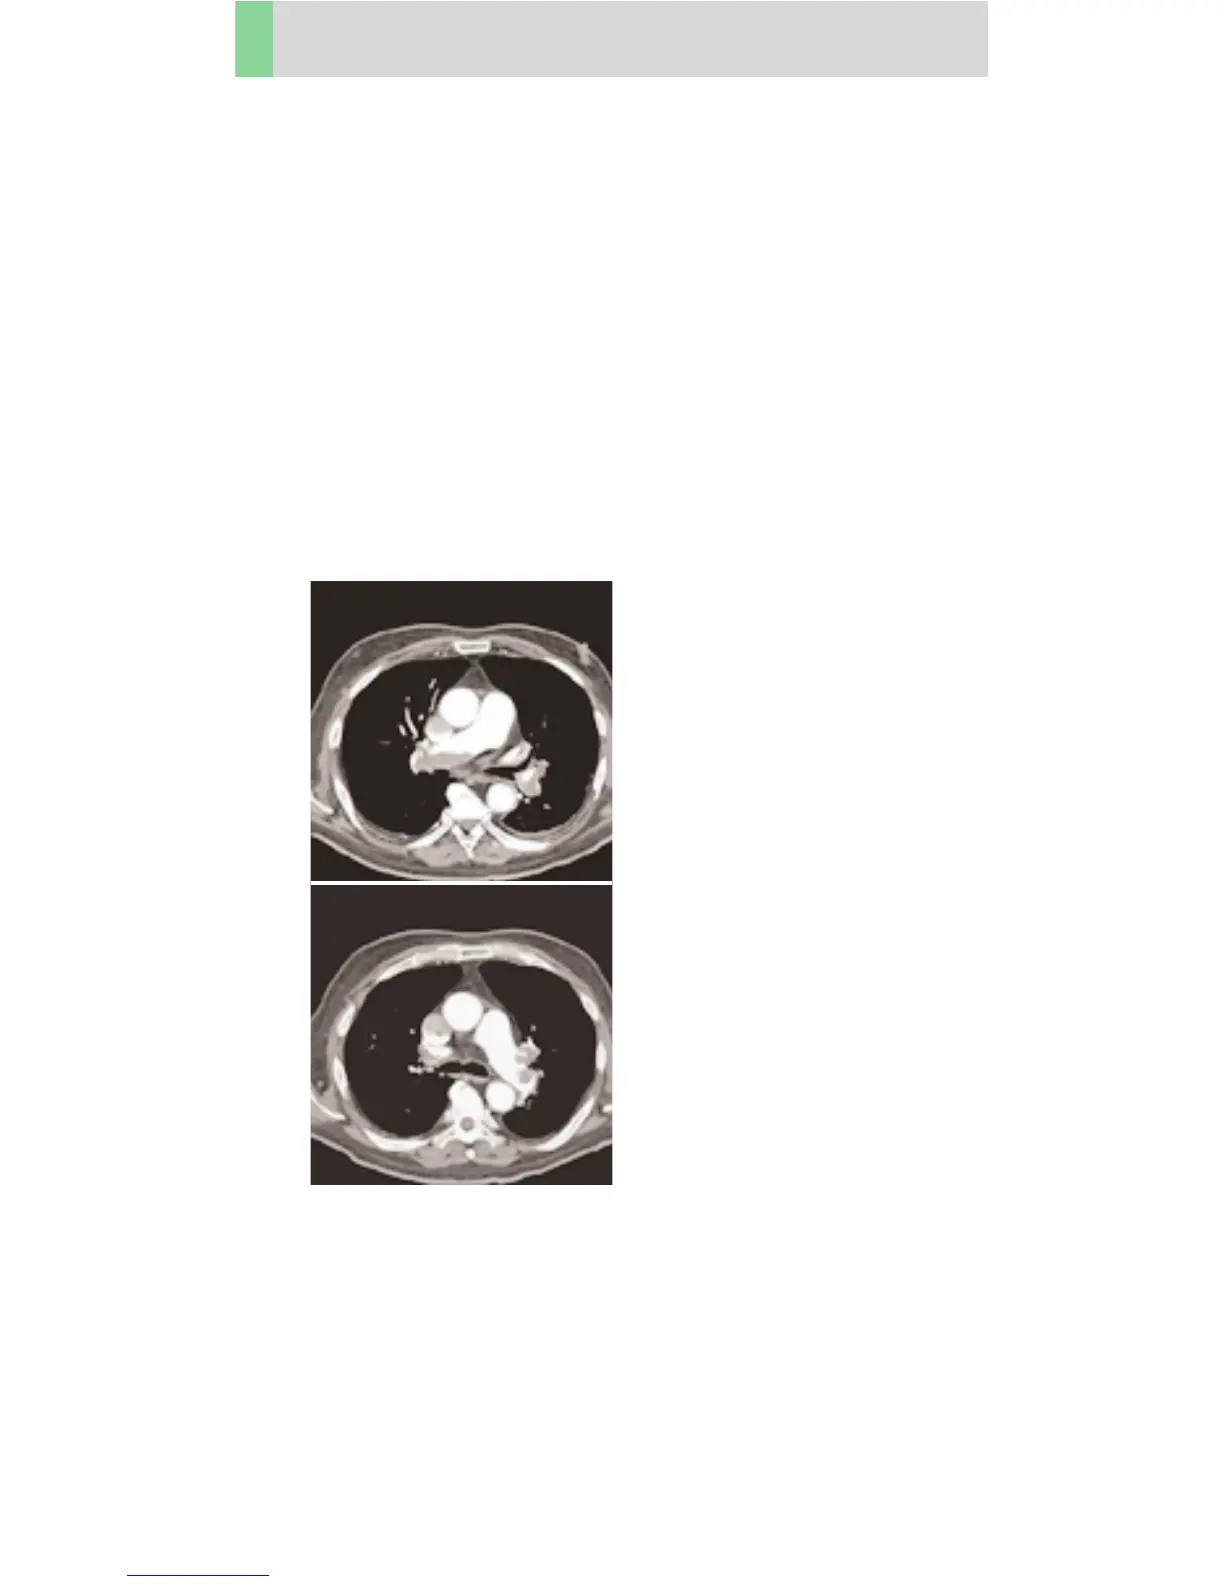

Thorax

Embolism06s

Indications:

Spiral mode for Pulmonary Emboli studies using a

rotation time of 0.6 s.

There are two recon jobs predefined. The first one,

with 3 mm slice thickness, for the mediastinum,

the second reconstruction, with 1.25 mm slice thickness,

used for postprocessing.

A range of 28 cm will be covered in 20 sec.